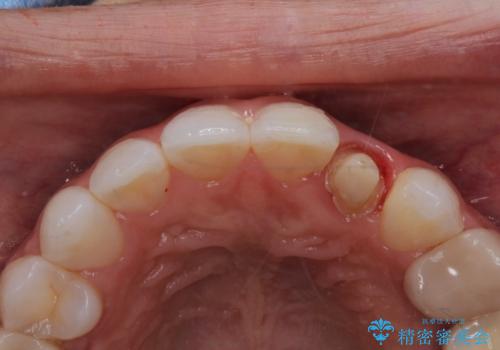

- 以前に被せ物の治療した箇所に汚れが溜まりやすいことを主訴に来院されました。

矯正治療を行なったのち、オールセラミッククラウンにて修復しております。